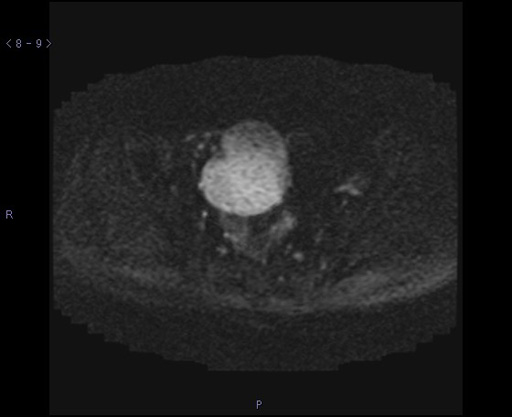

症例8:50代女性

下腹部痛にて来院。

図5 DWI axial